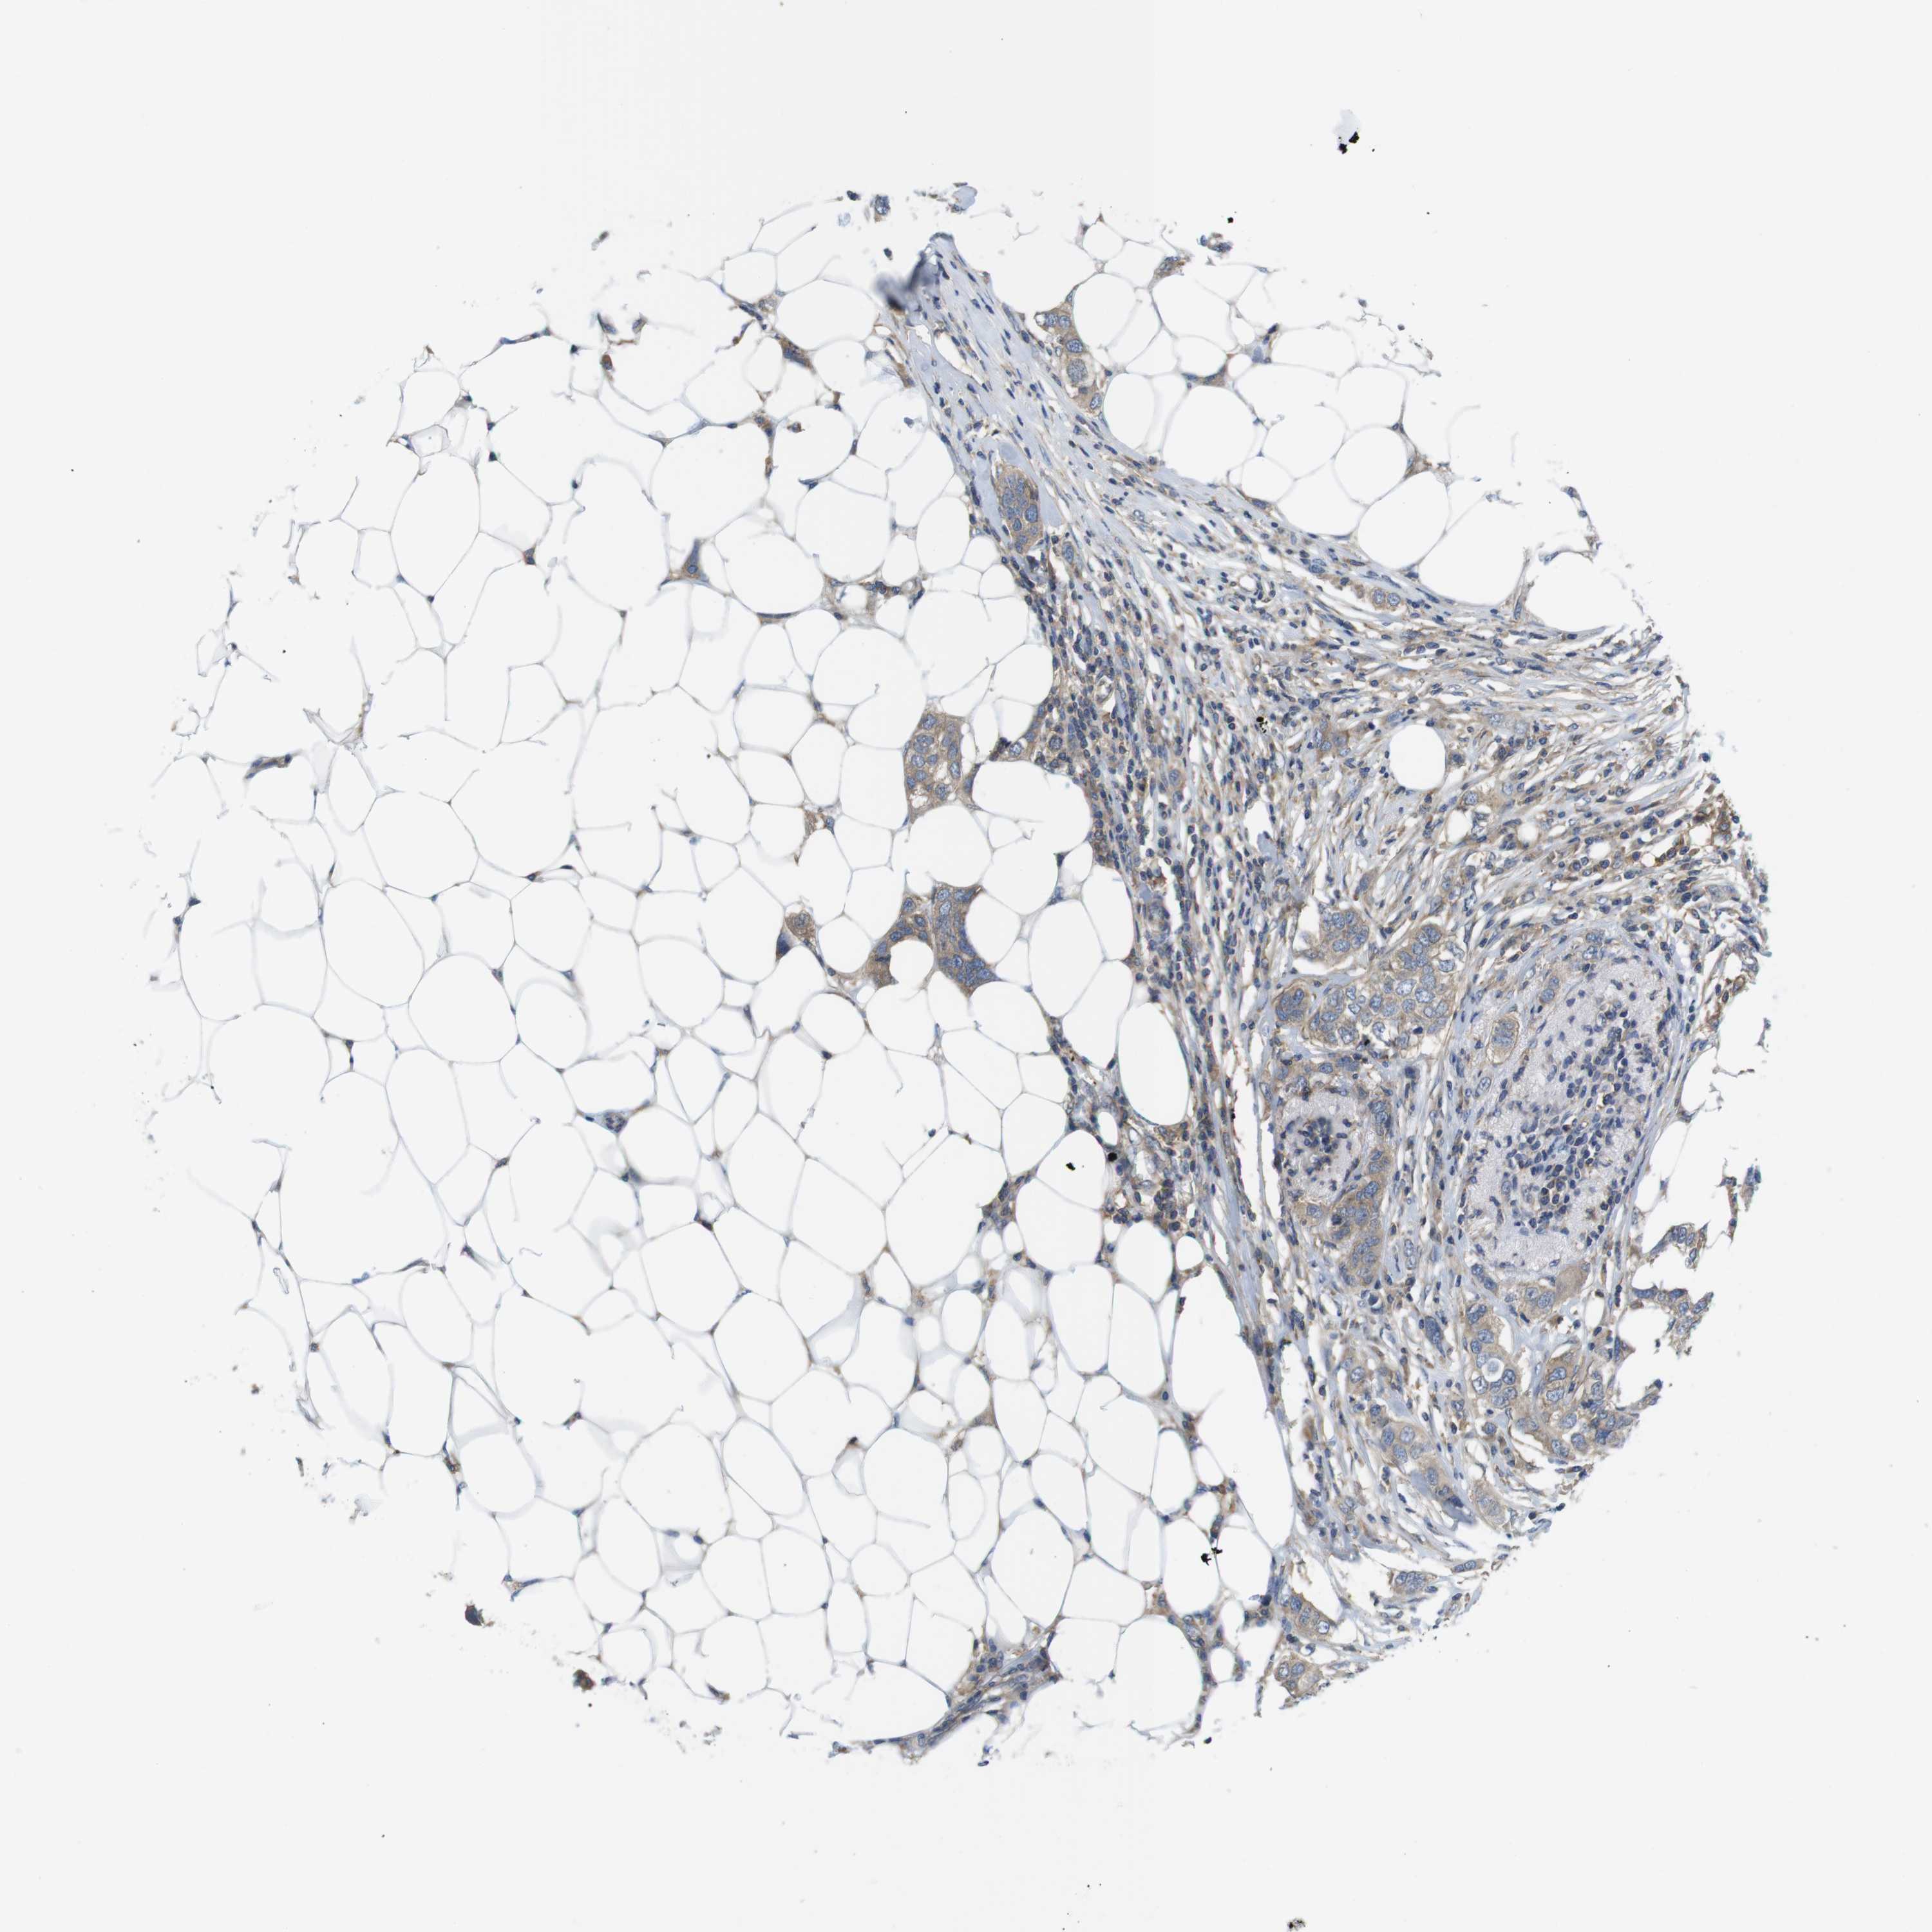

CANCER BREAST CANCER Show tissue menu

BRCA TCGA BRCA VALIDATION PROTEIN EXPRESSION